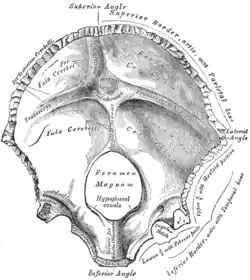

Occipital bone. Inner surface. | |

The cruciform eminence (or cruciate eminence) divides the deeply concave internal surface of the occipital bone into four fossae:

- The upper two fossae are called the cerebral fossae, are triangular and lodge the occipital lobes of the cerebrum.

- The lower two are called the cerebellar fossae, are quadrilateral and accommodate the hemispheres of the cerebellum.

The upper fossae are separated from the lower fossae by a groove for the transverse sinuses. At the point of intersection between all four fossae is the internal occipital protuberance.